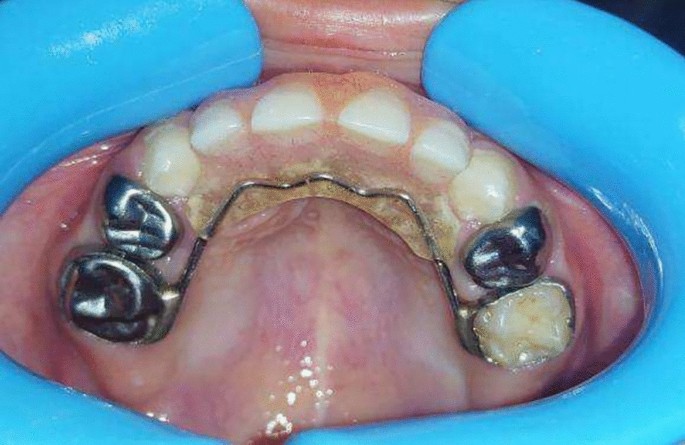

Group I (study group): Twenty preschool children used a modified fixed bridge in their anterior extraction site. (Fig1, 2, 3)

Premature loss of upper ant teeth.

Rehabilitation of extraction site with modified fixed bridge.

Palatal view of modified fixed bridge.

A modification was carried out in the bridge by split it through midline into two segments, then 1cm of stainless steel wire with diameter 0.8 mm was embedded into one segment (Male part) with free end, while the other segment a small tunnel was prepared to allow insertion of free end of the stainless steel wire into it (Female part) (Figs. 7, 8).

New Modified fixed bridge.

After fabrication of the modified bridge, it was received from the lab then temporary crowns were removed and the prepared abutment teeth were totally cleaned from any cement. Finally, the appliance was cemented with conventional glass ionomer cement.